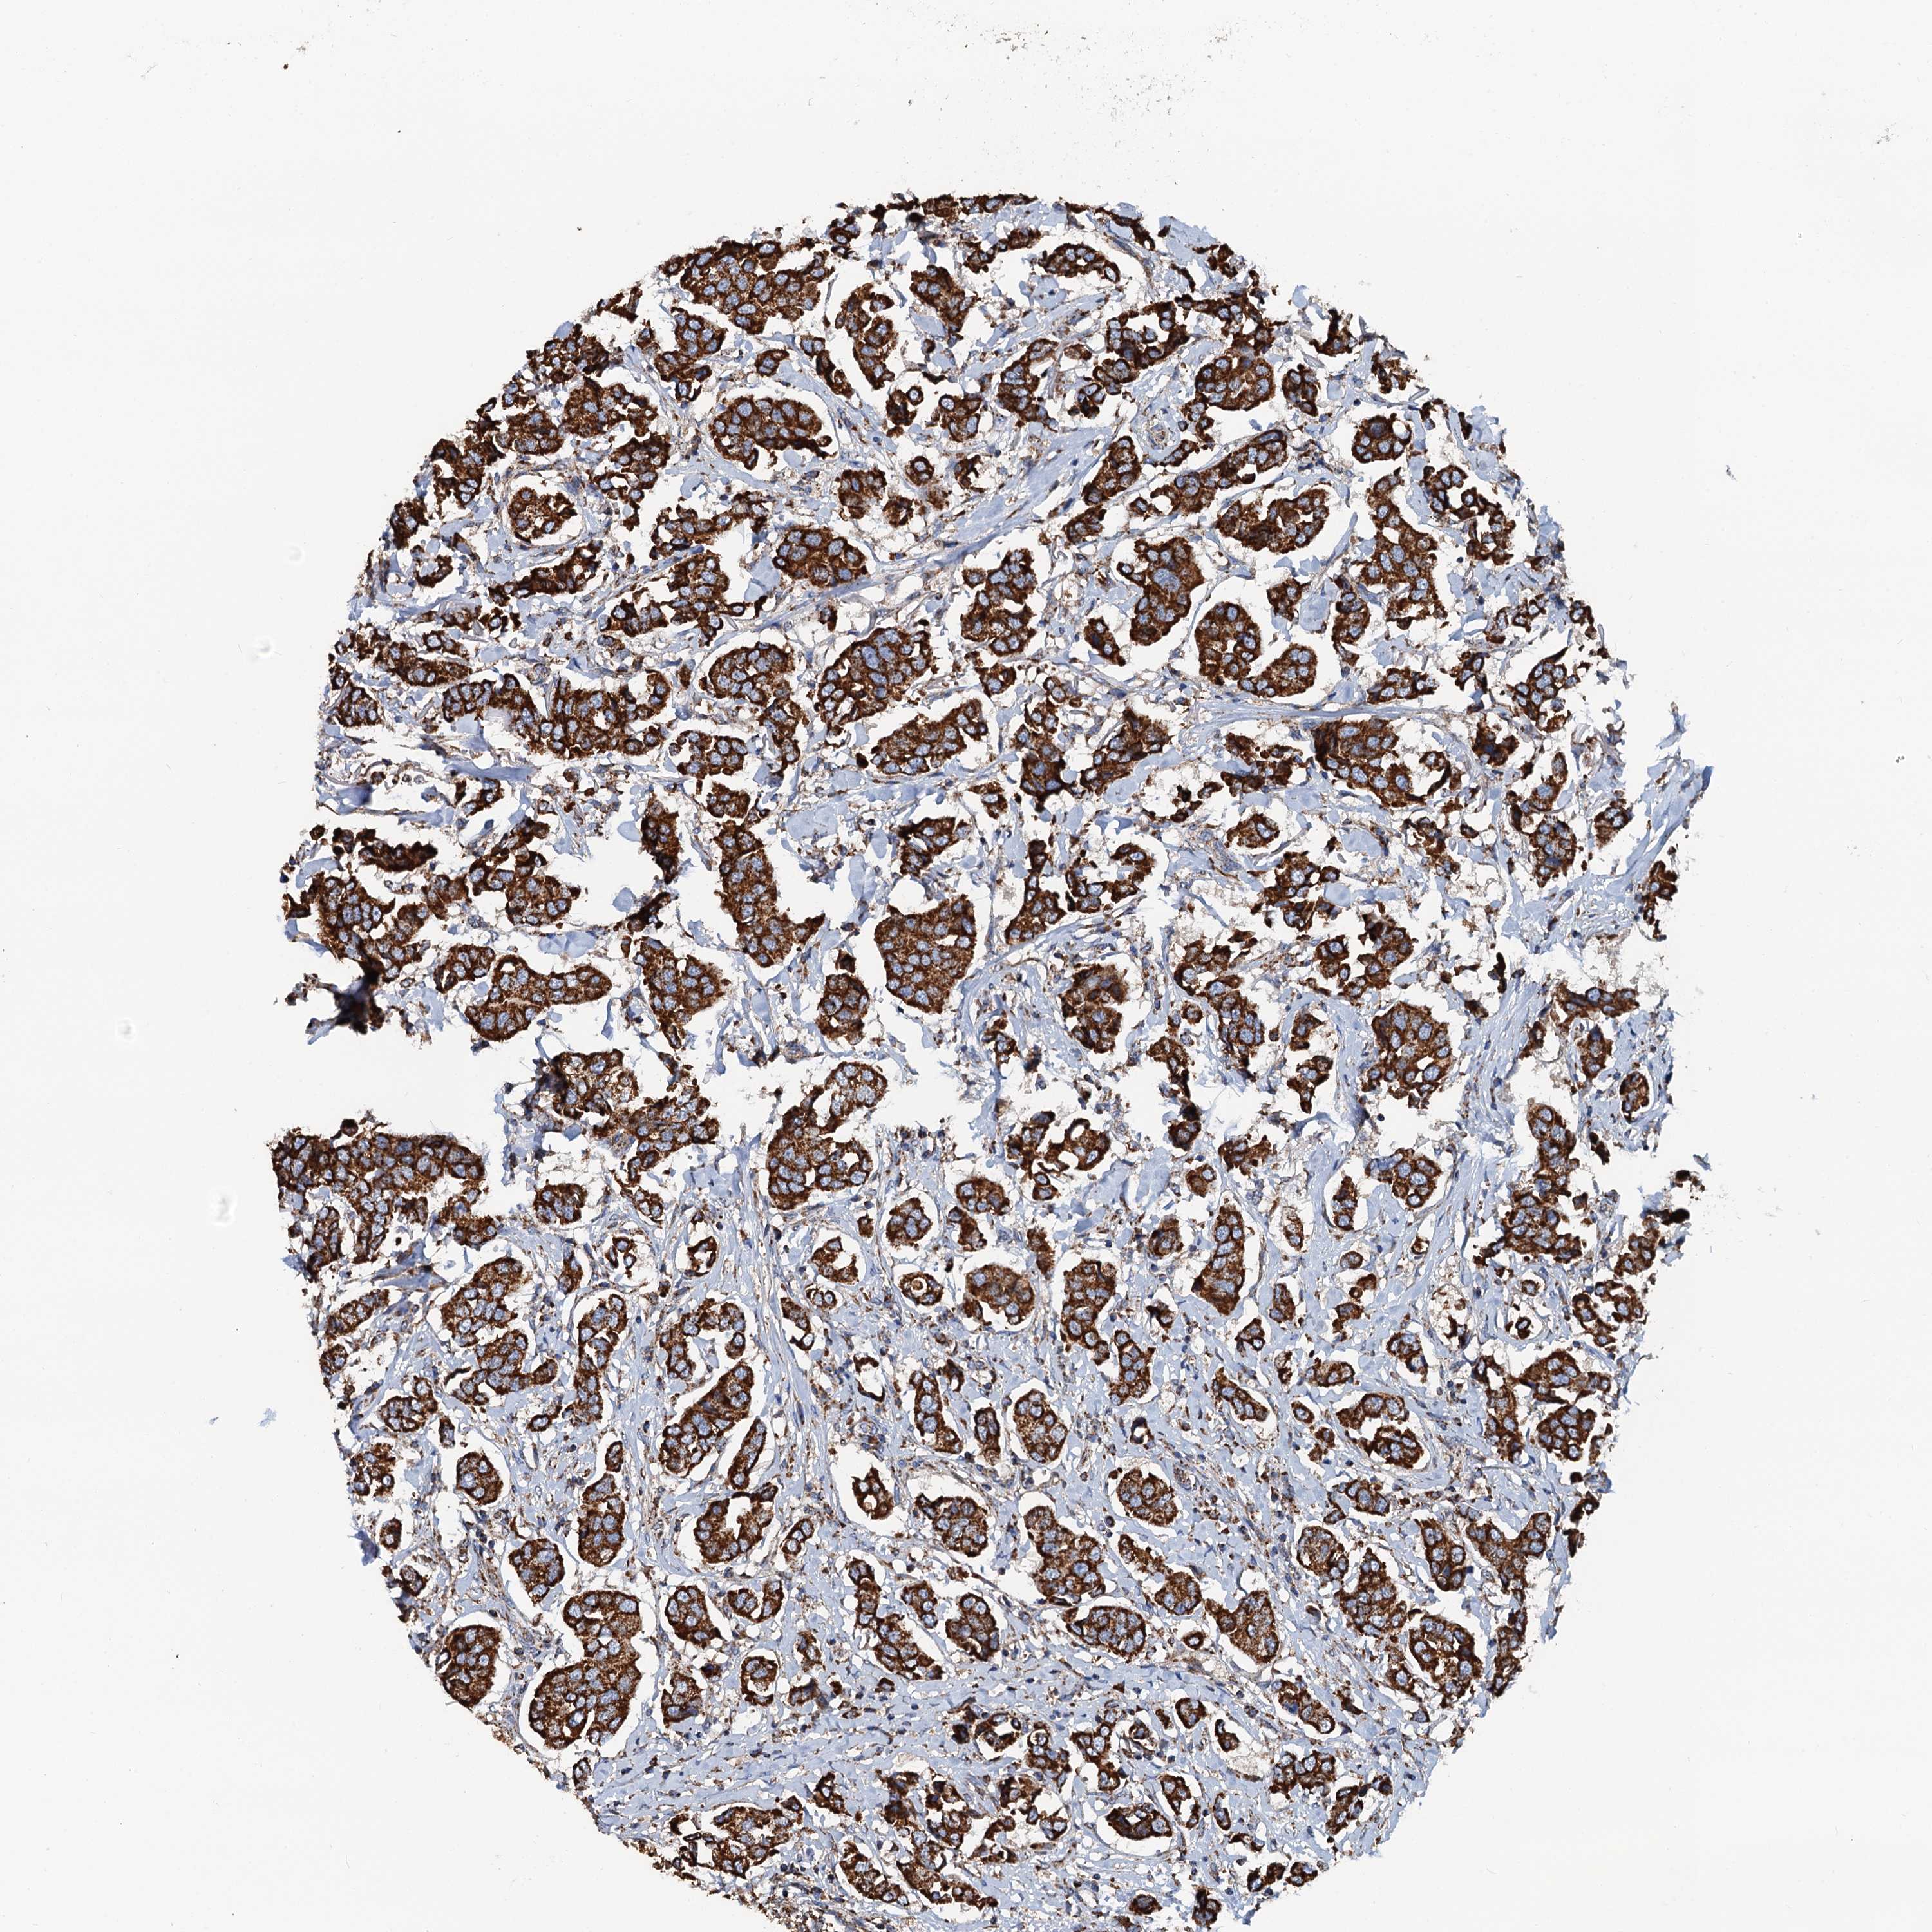

CANCER BREAST CANCER Show tissue menu

BRCA TCGA BRCA VALIDATION PROTEIN EXPRESSION